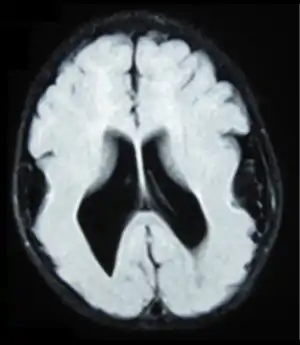

Lissencephaly (/ˌlɪs.ɛnˈsɛf.əl.i/, meaning 'smooth brain')[1] is a set of rare brain disorders whereby the whole or parts of the surface of the brain appear smooth.[2] It is caused by defective neuronal migration during the 12th to 24th weeks of gestation resulting in a lack of development of brain folds (gyri) and grooves (sulci).[3] It is a form of cephalic disorder. Terms such as agyria (no gyri) and pachygyria (broad gyri) are used to describe the appearance of the surface of the brain.

| Lissencephalic brain of a human, lacking surface convolutions (gyrification) | |